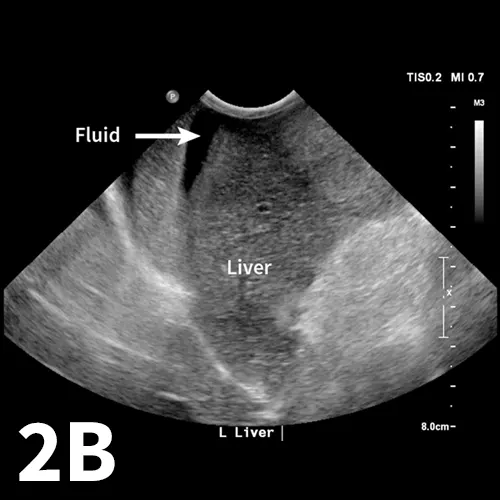

The aFAST examination divides the abdomen into 4 quadrants. A good way to perform the examination is to use a clock-face analogy and begin at the 12-o’clock position (Clock-face). The starting position, designated the diaphragmatic–hepatic (DH) position, is caudal to the xiphoid process; it is useful for finding fluid between liver lobes and the diaphragm. The next quadrant lies at the 3-o’clock position over the left flank and is designated the spleno–renal (SR) position. Both the spleen and left kidney should be visible within this region. At the 6-o’clock position over the caudal abdomen, the urinary bladder and colon can be seen, making this window the cysto–colic (CC) position. The final quadrant within the aFAST examination is over the right flank at the 9-o’clock position, designated the hepato–renal (HR) position. The right kidney and liver should be visible within this region.1,4

More than 10 years ago, a novel ultrasound protocol, abdominal focused assessment with sonography for trauma (aFAST), was described in veterinary literature1 and has changed the way emergency patients are evaluated for intraabdominal trauma. One of the most common signs of abdominal trauma is detection of free fluid within the peritoneal space. Most frequently, this fluid is a result of hemorrhage from blunt force trauma to the spleen or liver, although rupture of the urinary bladder or gallbladder is also a source of abdominal fluid in emergency patients. Before the widespread use of ultrasonography, blind abdominocentesis and radiography were the most readily available techniques to assess patients for peritoneal fluid. However, radiography has been shown to be less sensitive than ultrasonography, with ultrasonography experimentally being up to twice as sensitive as radiography with relatively small amounts of fluid (up to 2 mL/lb).2